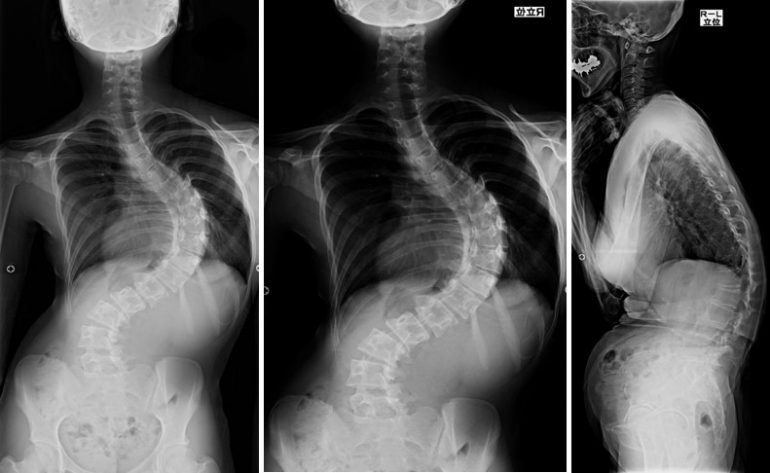

脊柱は背骨(脊椎)が柱状につながったもので、正常な脊柱は前や後ろから見てほぼまっすぐです。脊柱側弯症は脊柱が横(側方)に弯曲している病気で、原因があってその治療により弯曲が戻る一時的な機能性側弯と、脊椎のねじれをともなってもとに戻らない構築性側弯に大きく分けられます。構築性側弯には原因がわかってないものがほとんどを占め、骨のねじれをともなうケースもあります。

まずは立位姿勢や体幹の形について丁寧に診察をおこないます。背骨の変形を確認するため、立った姿勢でレントゲン撮影を行います。

治療方針を決める際、成長期のお子さんでは骨格の成熟度が最も大切になります。骨格が未成熟で、レントゲン撮影による弯曲(Cobb角)が20度以上あり、弯曲の進行が予測される場合は早期に治療が必要です。